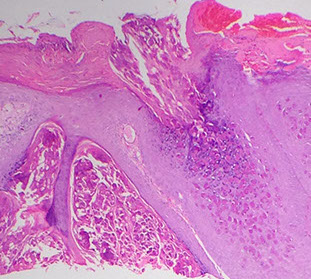

Grover disease - basal layer starting to break up with acantholysis

Acantholysis in Grover disease

Acantholysis and dyskeratosis (arrow) in Grover disease